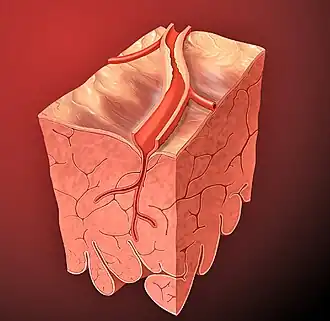

A isquemia em uma parte do cérebro leva ao acidente vascular cerebral (AVC), conhecido como "trombose" (embora nem sempre seja causada por trombos, pode ser também por estenose (estreitamento e/ou bloqueio de uma artéria). Nos membros pode causar gangrena e necessitar amputação. No pulmão pode levar a embolia pulmonar. No intestino é chamada de isquemia mesentérica e pode causar inflamação grave (colite isquêmica). Na pele resulta em descoloração, deixando a pele roxa ou azulada.

Se a isquemia chega a eliminar completamente o fornecimento de sangue ao tecido muscular cardíaco, ocorre privação da ATP e da fosfocreatina e acumulação de lactato, o que leva a uma ausência de contracção muscular cardíaca, que por sua vez leva a uma necrose (morte) celular dos tecidos isquémicos, obrigando à amputação de membros.